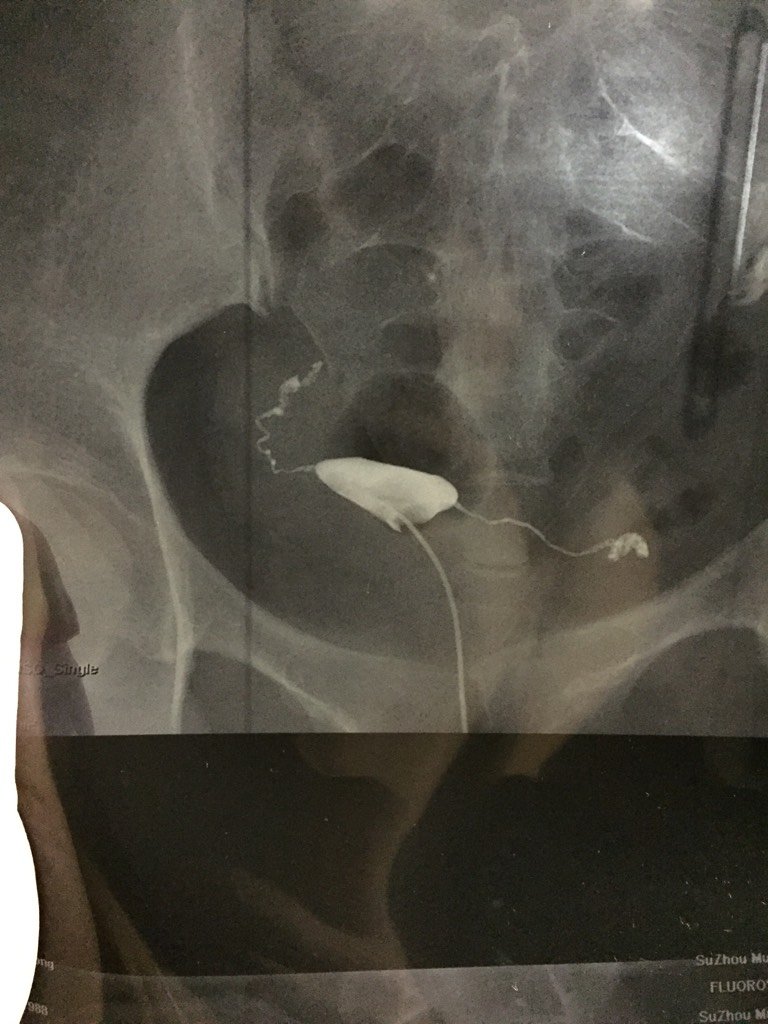

双侧输卵管显影通畅,远端管径扭曲、增粗,可见部分造影剂弥散到腹腔。24小时后盆腔摄片:可见造影剂大部分弥散到腹腔内。双侧输卵管走行区见多发斑点、片状造影剂残留。

你好,看你造影片子,是有盆腔炎,这张片子看不出弥散的情况,子宫偏向右侧,还有右侧输卵管上举迂曲,以及左侧远短增粗,这些都是盆腔炎的表现